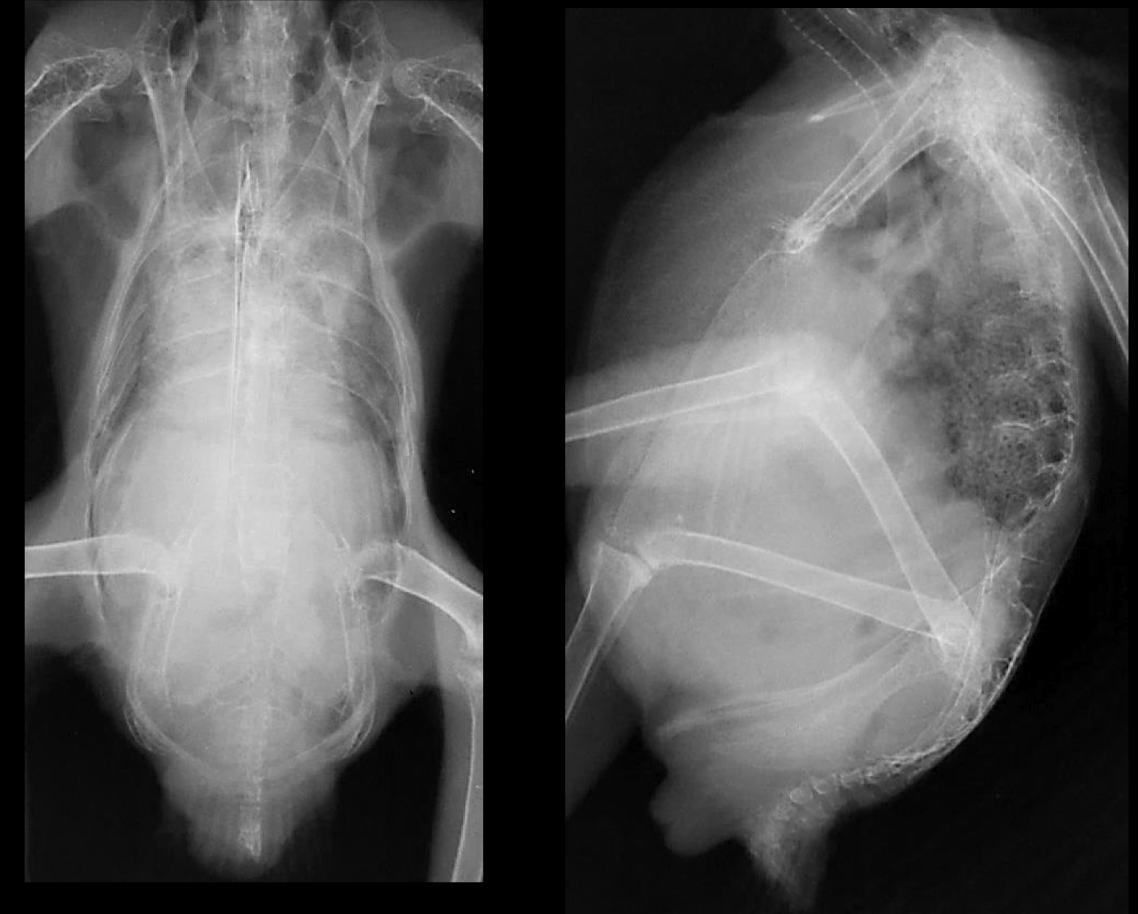

Correct radiograph positioning VD

Correct radiograph positioning Lateral